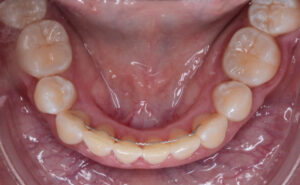

• Mantenedores de espacio.

Además, el no tratar una caries en un diente de leche puede provocar dolor, y hacernos tener que extraer ese diente antes de tiempo, provocando alteraciones en la mordida, que harán que necesitemos tratamientos de ortodoncia para corregir la malposición de los dientes definitivos como consecuencia de la perdida prematura del diente de leche.